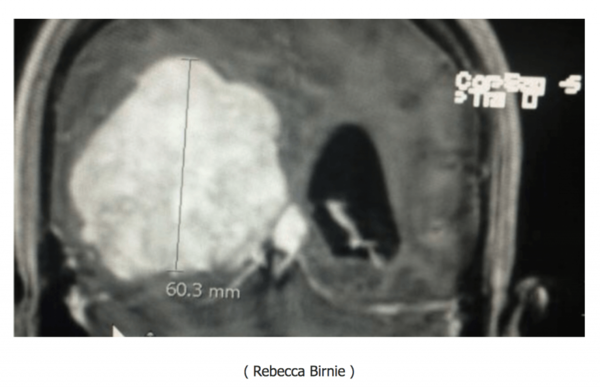

2016年7月,Rebecca在她母亲家中晕倒。她被送往送往安省北部的一家医院(Weeneebayko Area Health Authority),在那里她要求进行CT扫描。医生在她的大脑中发现了一个巨大的6厘米肿瘤,他们怀疑这个肿瘤已经生长了10年。

得知这个结果,Rebecca简直是哭笑不得,自己这么多年来的许多古怪的行为终于得到了解释,自己终于不用在被人误解成吸毒的人和精神病。